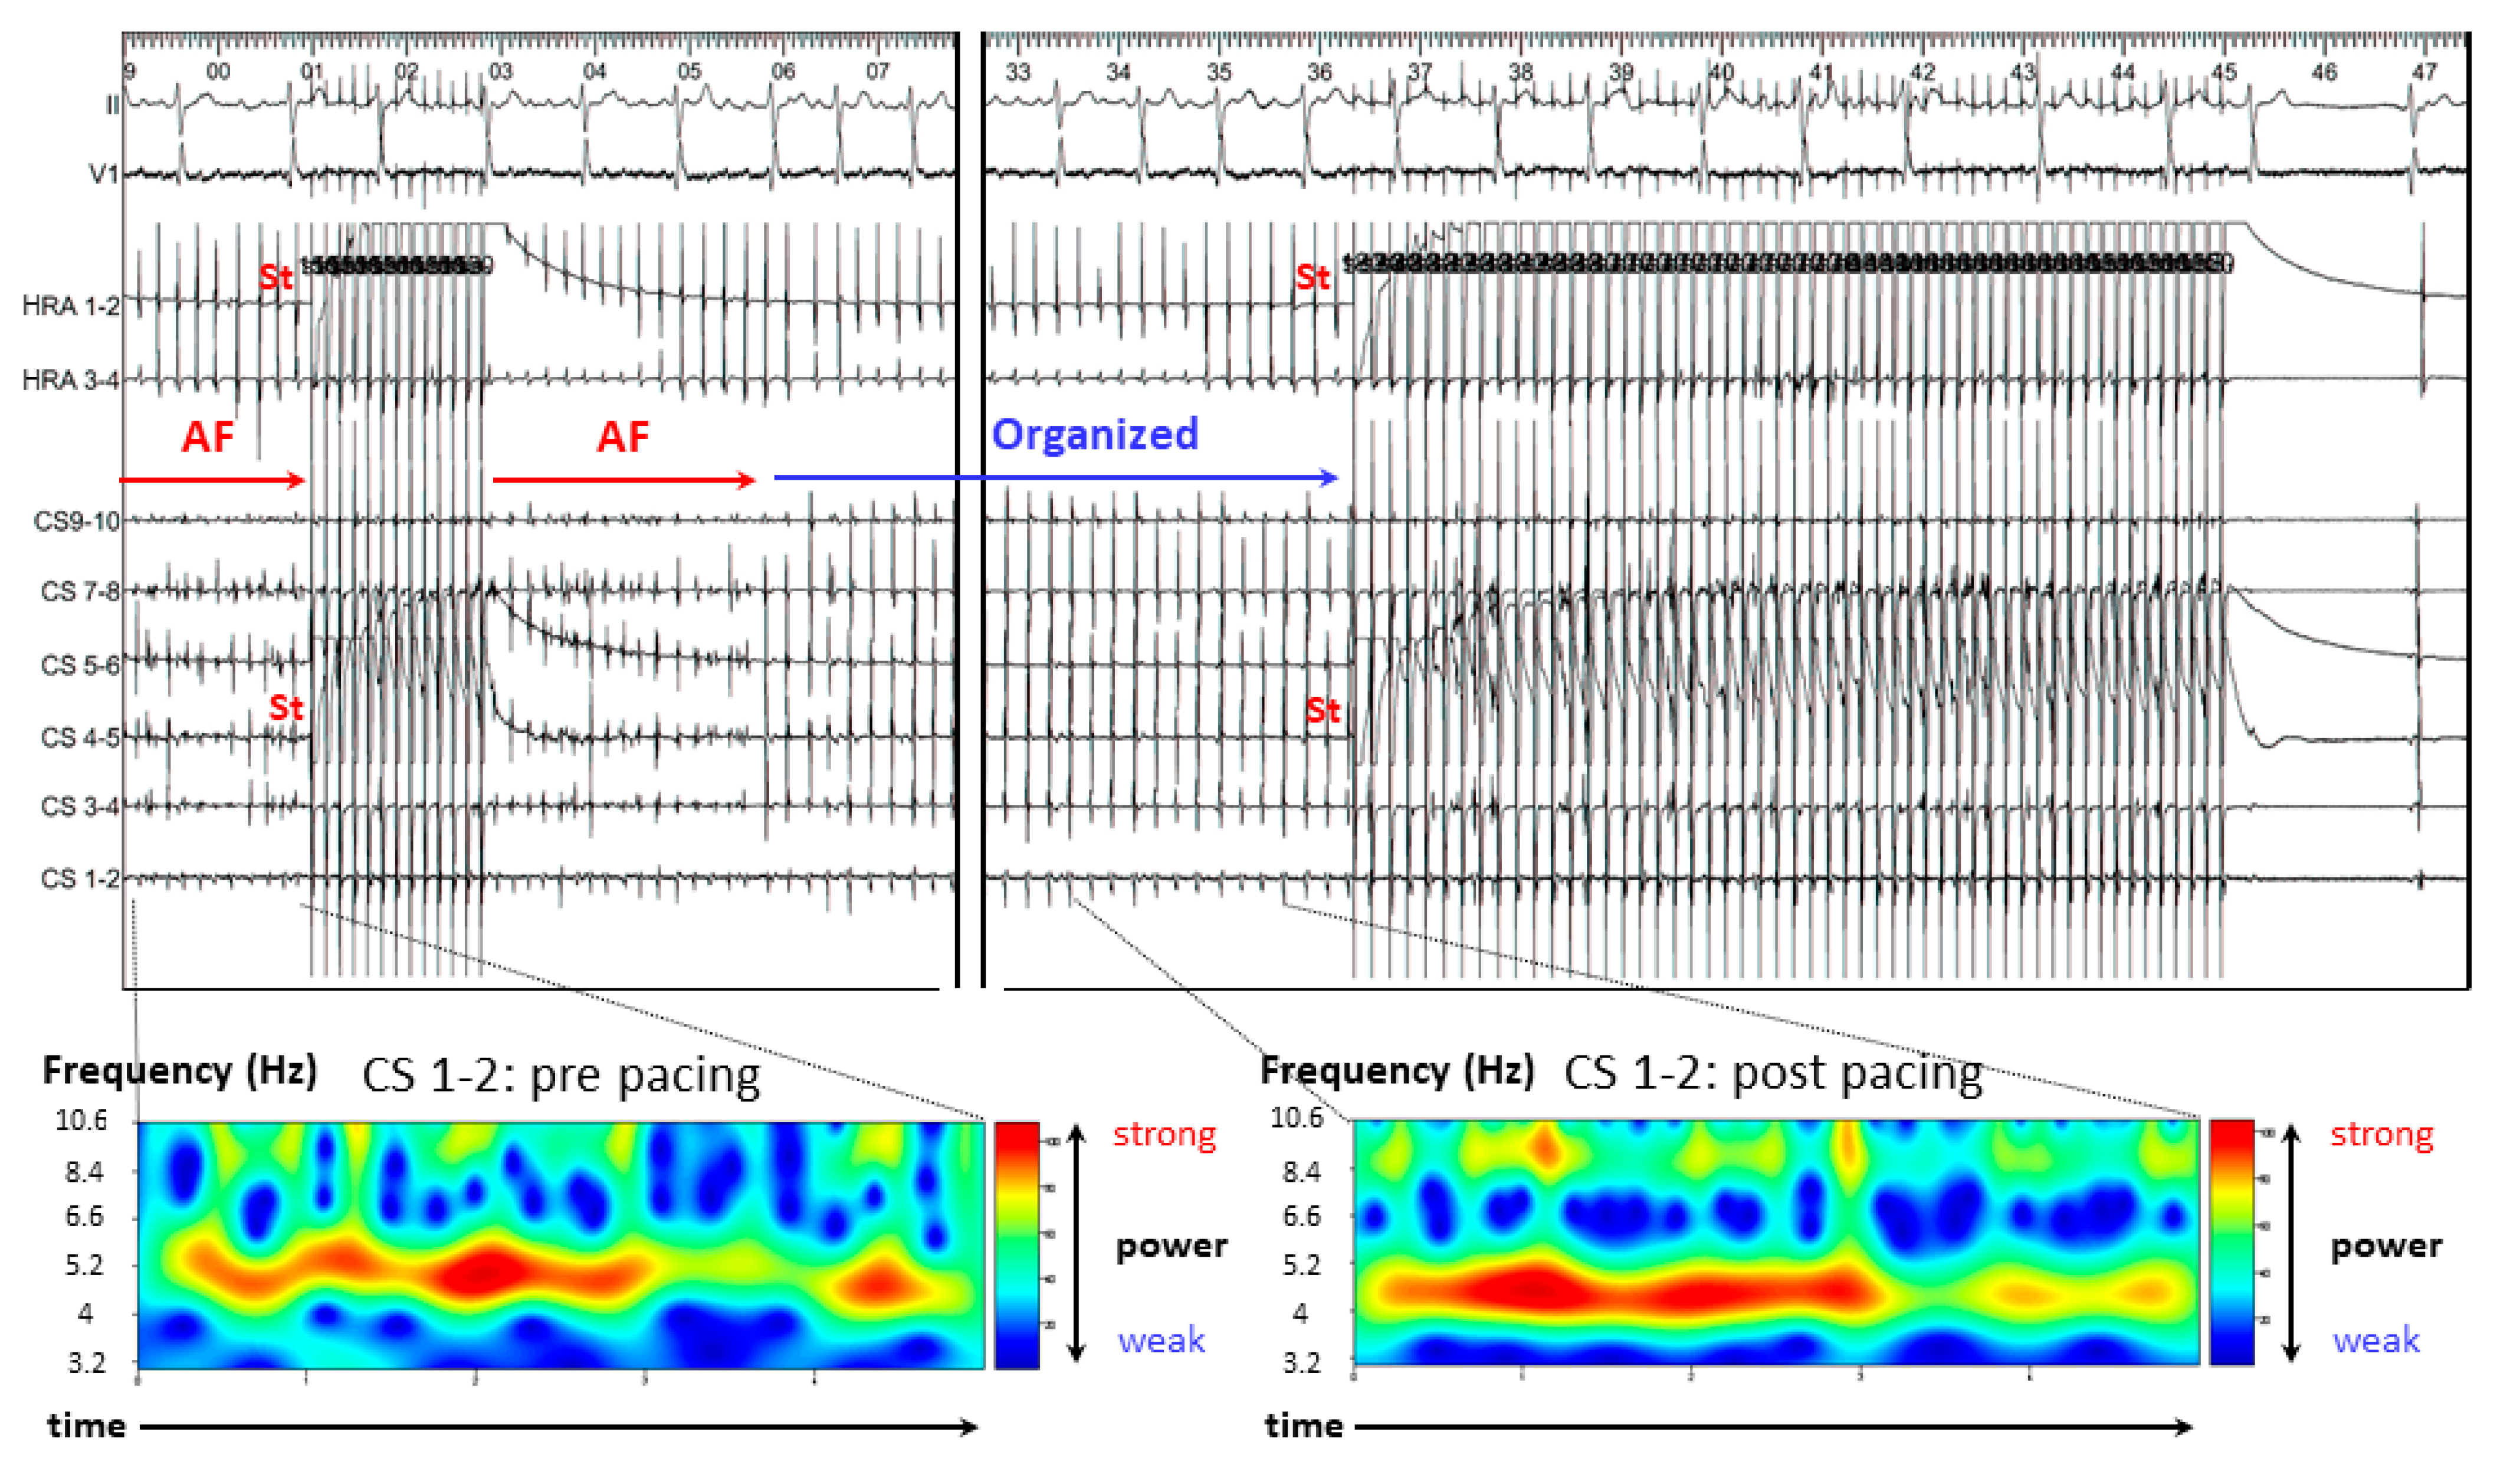

2.5. Continuous Wavelet Transform (CWT) Analysis

3.2.2. Case 2: 72-Year-Old Man with Symptomatic PAF

3.2.3. Case 3: 67-Year-Old Man with Symptomatic PAF